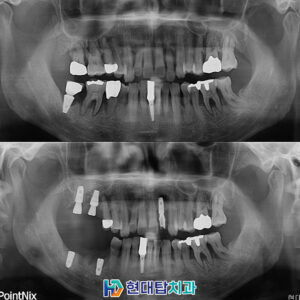

위 환자분은 52년생의 여성분으로

타원에서 진행하신 임플란트와 틀니를

사용 중이셨는데 틀니를 지지해 주던

치아가 파절되어 내원해 주셨습니다.

기존의 틀니를 사용하실 때부터

불편함이 많이 있으셨다고 하셔서

양쪽 위 8개의 임플란트를 식립하여

11개의 치아를 연결하는 브릿지의 형식으로

진행하기로 하셨고, 상태가 좋지 않던 오른쪽 아래

작은 어금니들은 신경치료 후 보철을 진행하였습니다.

또한 기존의 타원 임플란트 들의 보철물을

식립 예정인 임플란트와 교합이 잘 맞을 수 있도록

교체하도록 설명드렸고 치료 계획 수립하였습니다.

술후 파노라마입니다.

치아의 갯수가 많이 없다 보니

전체적으로 치아의 씹는 균형이 많이 무너진 상태여서

차근차근 맞춰가며 최종 보철까지 문제없이 합착하였습니다.

또한 예후가 불량했던 오른쪽 아래

작은 어금니들도 신경관 내부를 단단한 재료로

메워 신경치료를 진행한 후 보철까지 완료하었습니다.